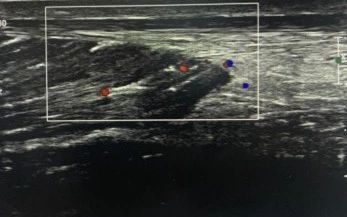

高質量發(fā)展|爲什麼(me)越來越多的骨科和運動醫學(xué)科患者,選擇肌骨超聲檢查?

腳崴了,關節疼痛,手腳麻木,肌肉拉傷……怎麼(me)辦?大多數人想到的是做X光、CT、核磁共振檢查。在北京前海股骨頭醫院有限公司,還(hái)有一種(zhǒng)手段被(bèi)廣泛應用于骨骼肌肉系統的疾...